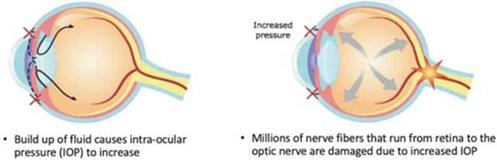

CBN is also the active ingredient in our second drug candidate, INM-088, which is in preclinical studies as a potential treatment for glaucoma. We are conducting studies to test INM-088’s ability to provide neuroprotection and reduce intraocular pressure in the eye. We compared several cannabinoids, including CBD and THC, to determine which cannabinoid was the best drug candidate for the treatment of glaucoma. Of all the cannabinoids examined in preclinical studies, CBN demonstrated the most optimal neuroprotection effect. Furthermore, CBN also exhibited intraocular pressure reduction capability. INM-088 is in advanced formulation development.

Current treatments for glaucoma primarily focus on decreasing fluid build-up in the eye. Our data has shown that INM-088 may provide neuroprotection in addition to modulating intraocular pressure by improving drainage of fluid in the eye. Thus far, we have conducted numerous preclinical pharmacology studies to demonstrate these effects.